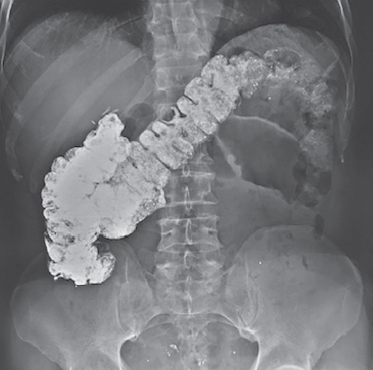

С февраля 2018 г. у пациента появились периодические боли в пояснице справа. В мае с приступом правосторонней почечной колики лечился в центральной районной больнице, где на УЗИ выявлено расширение лоханки справа до 32 мм, чашечек — до 10 мм, но после купирования колики лоханка сократилась до 19 мм. Больной снова консультирован онкоурологом — диагноз «Хронический пиелонефрит. Стриктура правого мочеточника? Опухоль правого мочеточника?». Рекомендовано дообследование в областной клинической больнице. При обследовании при УЗИ почек выявлено с правой стороны расширение лоханки до 28 мм, чашечек — до 17 мм, пиелоуретерального отдела — до 10 мм. При обзорной урографии обнаружены выраженные остеофиты смежных углов L1-L2 справа до 2,5 см в длину, возможно, травмирующие лоханку. На экскреторных урограммах лоханка справа расширена, правый мочеточник в прилоханочном отделе расширен до 0,9 см, извитой (рис. 1). Ниже на протяжении 2,0–2,5 см просвет мочеточника резко сужен (стриктура, периуретерит?).

Рис. 1. Пациент З., 68 лет. Экскреторная урограмма: 1 — стриктура мочеточника; 2 — остеофит

Fig. 1. Patient Z., age 68. Excretory urography: 1 – ureteral stricture; 2 – osteophyte